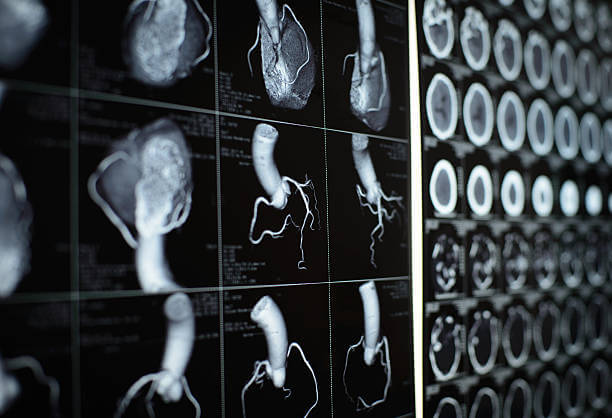

협심증 진단

- 환자의 증상과 의료 기록을 종합적으로 검토합니다. 가슴 통증, 호흡 곤란, 피로 등 협심증과 관련된 증상을 확인합니다.

- 의사는 환자의 혈압, 맥박, 호흡 등을 검사하여 신체적인 이상을 확인하고 심장 관련 소리나 이상 징후를 살펴봅니다.

- 혈액 검사를 통해 콜레스테롤 수치, 혈당 수치, 염증 표지자 등을 확인하여 협심증 가능성을 평가합니다.

- 심전도는 심장의 전기 활동을 측정하여 심장의 기능과 리듬을 평가합니다.

- 환자는 운동이나 약물을 통해 심장의 반응을 측정하는 스트레스 테스트를 받을 수 있습니다.

카테터 기술 및 수술: 협심증이 심각한 경우, 혈관 조영술이나 관상동맥 우회 수술 등의 카테터 기술이나 수술을 통해 혈관을 개선하거나 우회하는 조치를 취할 수 있습니다.